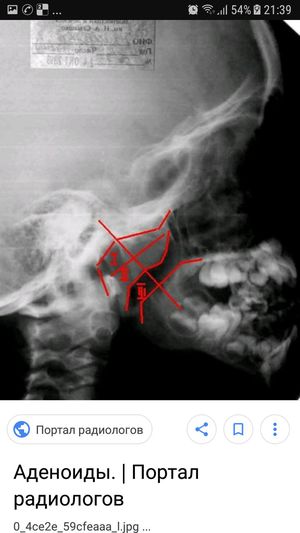

Adenoids

It is inflammation of the nasopharyngeal tonsil, adenoides (lat.)